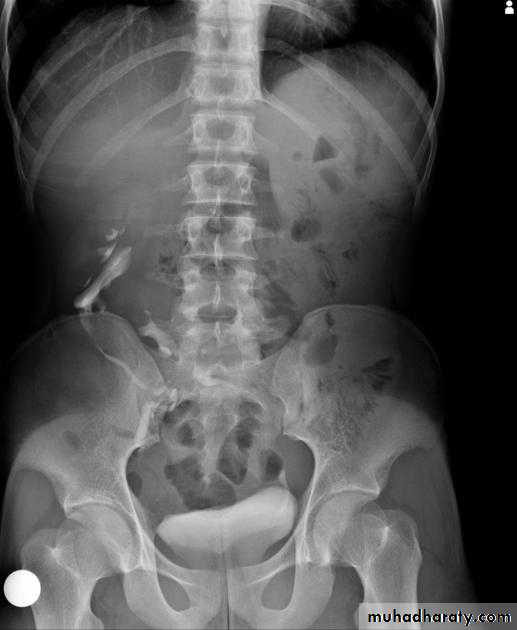

Normal IVU

nephrogram